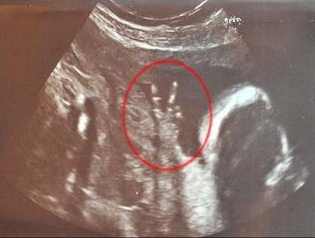

[婴儿话题(bis 18M)] 未出生小婴儿在英国妈妈肚里比出V字胜利手势(图)

难道要赢在起跑点上?据台湾东森新闻报道,即将为人母的英国女子卡罗琳巴恩斯已怀孕23周。最近她去照超声波,结果发现肚子里的孩子竟然比出结结实实的V字型胜利手势。

目前35岁,在电视台担任分区经理的卡罗琳说:“医院里的护士笑到不行。在照超声波的整个过程中,他的手势都是这个样子。”